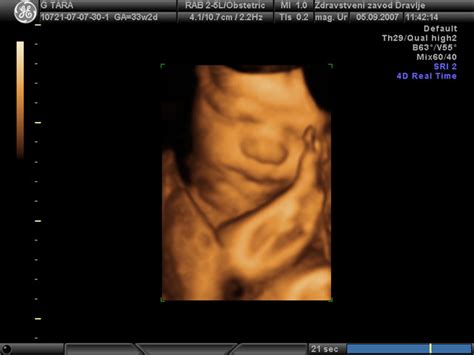

Ultrazvok je nepogrešljivo orodje v sodobni ginekologiji in porodništvu, ki omogoča spremljanje razvoja ploda ter zgodnje odkrivanje morebitnih nepravilnosti. Poleg diagnostične vloge ultrazvok pogosto ponuja tudi vpogled v spol otroka.

Morfologija ploda: Podroben ultrazvočni pregled, ki ga izvajamo med 20. in 22. tednom nosečnosti, predstavlja ključen trenutek za oceno razvoja otroka. Poleg zgodnje morfologije (meritev nuhalne svetline) pri tem UZ odkrijemo največ razvojnih napak. Preiskavo začnemo s srčnim utripom ploda, pogledamo lokacijo posteljice in količino plodovnice. Nato preverimo razvoj in rast organov in organskih sistemov v telesu otroka, vključno s popkovnico. V času morfologije ploda se spol otroka običajno že dobro vidi, saj so zunanji spolni organi dovolj razviti.